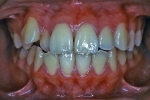

| 初診時